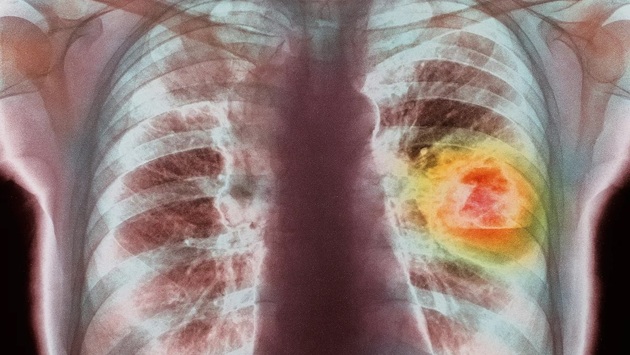

В МФТИ идут испытания уникального российского препарата против рака легких

Лекарство до конца текущего года пройдет серию тестов in vitro (в пробирке), а затем наступит черед доклинических и клинических исследований. Примечательно, что препарат уничтожает только пораженные раком клетки и при этом бережно относится к здоровым тканям.

Завлабораторией доклинических исследований Института биофизики будущего МФТИ Антон Алашеев уточнил, что на фоне санкций направление таргетной терапии очень актуально. По данным «Газеты.Ru», разработке предшествовал кропотливый предварительный этап.

«(...) вокруг каких онкомишеней сейчас «ажиотаж» в мировой фарминдустрии. Это оказались ингибиторы KRAS. На данный момент уже зарегистрированы два действующих вещества на их основе: соторасиб и даграсиб»‎, — уточнил Алашеев.